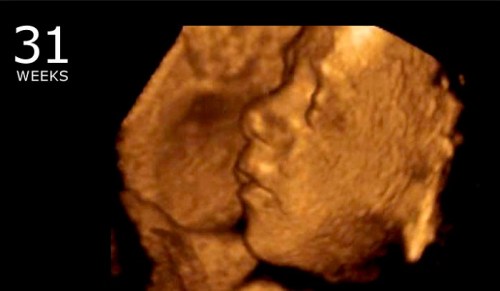

My grandson was born at 35 weeks. He went home from the hospital after only 8 days.